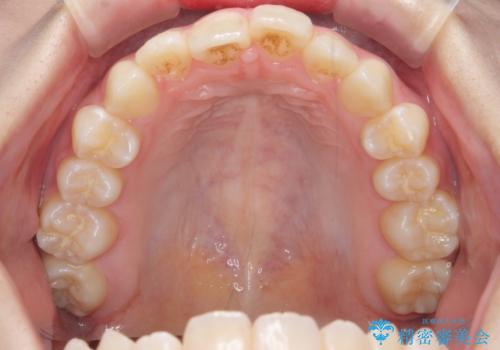

[ インビザラインライト ] 短期間で前歯だけを並べたい

担当医 大元洋佑